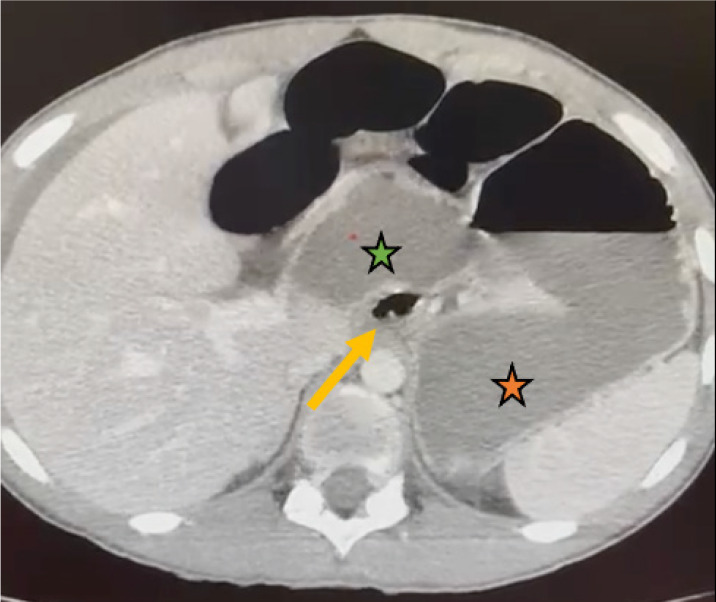

Abdominal internal hernia is a rare cause of intestinal obstruction in pediatric emergency departments, being the herniation through the foramen of Winslow an exceptional entity (less than 0.5% of the herniae). We report the case of a 15-year-old adolescent male without previous surgical interventions who presented with abdominal pain and vomiting; computed tomography scans showed intestinal obstruction due to an internal hernia through the foramen of Winslow. To reduce the herniated ileum, the patient required surgical intervention with diagnostic laparoscopy, which, due to bad visualization, was changed to supraumbilical midline laparotomy. There was no need to resect the affected ileum as it appeared healthy. We did not perform a preventive technique to reduce the risk of recurrence. Postoperative pelvic collection was conservatively managed with antibiotics. The patient undergoes regular follow-up in the pediatric surgery department.